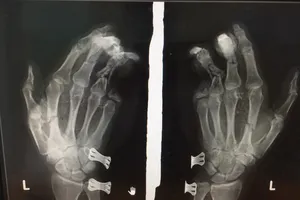

Điện thoại phát nổ khi đang sạc khiến nam thanh niên bị dập nát bàn tay Y tế - Sức khỏe 27/05/2020 15:05